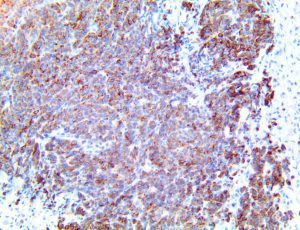

It is the ICU physician who is most likely to witness one of the deadliest manifestations of the abnormal immunological response, the cytokine storm syndrome (CSS). This response is also referred to by some as the cytokine release syndrome (CRS). CSS is characterized by continuous activation and expansion of macrophage and lymphocyte populations, which secrete large amounts of cytokines, causing the cytokine storm. This massive cytokine release is akin to hemophagocytic lymphohistiocytosis (HLH) disease, a syndrome characterized by initial unchecked and persistent activation of cytotoxic T lymphocytes and NK cells.

Clinical and laboratory manifestations of HLH include fever, enlarged liver and/or spleen, neurologic dysfunction, coagulopathy, liver dysfunction, cytopenias (i.e., low levels of erythrocytes, leukocytes, and/or platelets), hypertriglyceridemia, hyperferritinemia, hemophagocytosis, and eventually diminished NK cell activity as the immune system becomes progressively paralyzed. HLH can be familial (primary HLH) or secondary to another disease process (sHLH), such as rheumatic disease, in which it is referred to as macrophage activation syndrome (MAS, characterized by elevated ferritin).